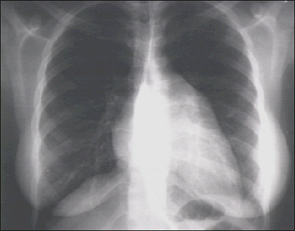

PA and Lateral

Click on the xrays to enlarge them.

Choose the best interpretation of the chest X rays:

Left atrial enlargement and right ventricular enlargement

Left ventricular enlargement and pulmonary congestion

Calcified mitral annulus

Left ventricular enlargement and dilated aorta

Left ventricular enlargement and left atrial enlargement